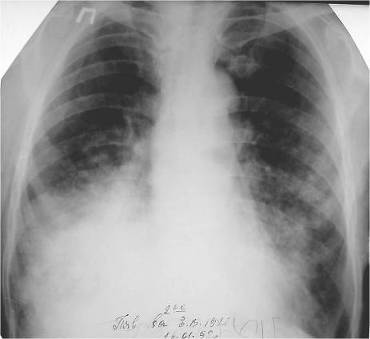

Периферический рак составляет 20-30% от общего числа случаев рака легкого и около половины всех солитарных узловых образований.

Периферический рак длительное время развивается скрыто. Клинические симптомы обычно появляются в том случае, когда опухоль распространяется на соседние органы, на средостение, грудную стенку. Тогда больные предъявляют жалобы на боли в груди. При прорастании опухоли в крупный бронх появляется кашель и кровохарканье. В поздних стадиях появляются признаки интоксикации: слабость, утомляемость, потеря аппетита. В связи с этим своевременное выявление периферического рака - в первую очередь прерогатива рентгенологического исследования.

Одной из причин ошибочной диагностики периферического рака является неправильная трактовка рентгенологической картины. В сознании врачей периферический рак часто ассоциируется с округлым "шаровидным" образованием. Между тем периферический рак на разных этапах развития имеет разную макроморфологическую и и рентгенологическую картину.

Общепринятое мнение о шаровидной форме периферического рака справедливо только по отношению к относительно большим узлам, диаметр которых превышает 3-4 см. Большинство более мелких опухолей не имеет шаровидной формы и приобретает таковую только по мере роста новообразования. Сравнительно маленькие опухоли имеют вид очага уплотнения неправильной, амебовидной или звездчатой формы, неоднородной структуры с нечеткими, неровными контурами.

Иногда опухоль имеет несколько центров роста и выглядит в виде конгломерата сливающихся очагов уплотнения. Большое значение в диагностике периферического рака имеет симптом лучистости в виде веерообразно расходящихся отростков по периферии опухоли, так называемая Corona maligna (Приложение А рисунок 1). Этот симптом наблюдается примерно в 2/3 случаев периферического рака. Считается, что лучистость легочного рисунка вокруг опухоли, так же как и втяжение прилежащей утолщенной плевры, является выражением не только ракового лимфангита, но и сморщивания опухоли. Одновременно с ростом опухоли в ней развиваются некробиотические процессы, которые стимулируют реактивную и стромогенную реакцию соединительной ткани. Вследствие этого в зоне опухоли формируется нечто, подобное звездчатому рубцу.

Опухолевый очаг на ранних стадиях развития обычно имеет неоднородную структуру. Основной причиной неоднородности является мультицентричность и неправильная форма роста, реже она объясняется распадом опухоли. На рентгенограммах впечатление неоднородности структуры раковой опухоли усиливается за счет наслоения нормального или патологически измененного легочного рисунка, в особенности, если он по тем или иным причинам усилен.. G. Rigler в 1955 г. описал характерный для злокачественных опухолей легких симптом зарубки или вырезки - локальное втяжение медиального контура опухоли, обусловленное, вероятно, обрастанием опухолью прилежащего крупного сосуда (Приложение А рисунок 4,5). Этот симптом встречается относительно редко, не более чем у 8-10% больных.

Когда опухоль прилежит к междолевой щели, можно видеть легкое втяжение утолщенной плевры (симптом паруса).

Контуры сравнительно небольших периферических опухолей в большинстве случаев нечеткие. Это свидетельствует о том, что на ранних стадиях развития раковый процесс имеет склонность к инфильтративному росту. Позднее, когда размеры опухоли превышают 2,5 см диаметром, ее контуры становятся бугристыми, но более четкими.

На более поздних этапах развития появляется дорожка ракового лимфангита, связывающая опухоль с корнем. Различают два вида дорожек: одна из них - в виде неоднородной тяжистости за счет периобронхиальной и периваскулярной опухолевой инфильтрации, вторая - однородная, широкая, связанная с цепочкой метастатически измененных лимфоузлов или с ростом самой опухоли. В корне появляются увеличенные лимфоузлы. В этих случаях говорят о фазе биполярности. Распространение опухолевого процесса на крупный бронх вызывает его обструкцию, присоединяется ателектаз - происходит так называемая централизация периферического рака. Однако симптом "дорожки к корню" для постановки диагноза периферического рака самостоятельного значения не имеет, т.к. может встречаться и при других заболеваниях (туберкулезе, хронической пневмонии). Отмечается, что при раке (в отличие от туберкулеза) в дорожке редко виден дренирующий бронх.

Таким образом, периферический рак на разных стадиях эволюции имеет разную рентгенологическую картину, и, следовательно, дифференциально-диагностический ряд в каждом случае иной. На ранних стадиях развития периферический рак чаще всего похож на очаг воспаления или пневмосклероза и гораздо реже напоминает доброкачественную опухоль или кисту.